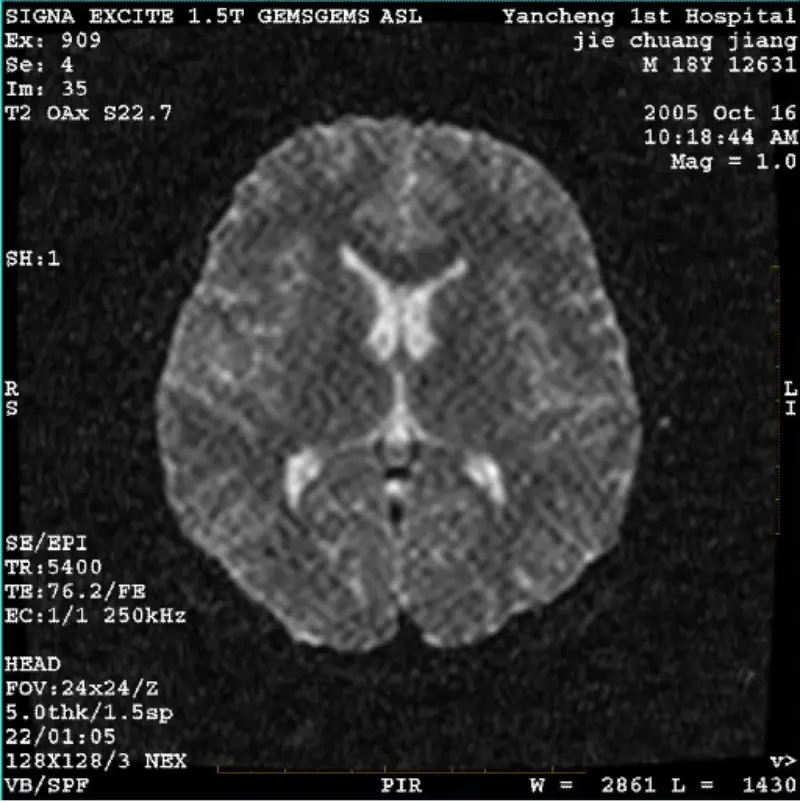

Olvass továbbRENDSZER: 1.5T Signa Twin Excite II (11.0M4 szoftververzió) PROBLÉMA/TÜNET DWI (zoom mód és teljes mód) és fiesta (zoom mód és teljes mód) képpel rendelkezik látható hálózatos vagy kordbársony műtermék, függetlenül attól, hogy testtekercset vagy fejet használ tekercs, más rutinkép normálisnak......